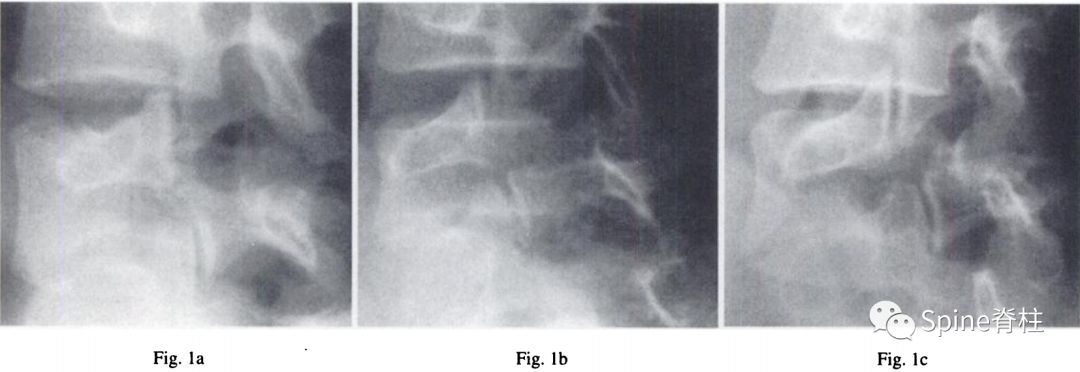

1. 峡部裂的Morita分型

• 早期 (early):可见峡部骨折线

• 进展期 (progressive):骨折断端间隙增宽

• 终末期(terminal): 假关节形成

图:早期(a),进展期(b),终末期(c)

随后,Sairyo教授进一步CT研究,将Morita分型早期又分为最早期(very early): 骨折线模糊或不连续的骨折线和晚早期(late-early): 骨折线清晰明显。

图:腰5双侧峡部裂,右侧为最早期,左侧为晚早期